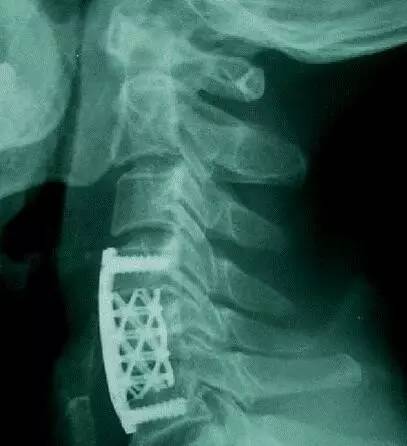

用来替换4节颈椎的3D打印内植物(是不是跟想象中的完全不一样,做成这样是有原因的,后文会告诉你)。该内植物通过两端的接头直接固定在第一节和第六节椎骨上。它的力学强度和与上下椎骨的接触面积,都明显大于传统的钛网。一段时间后,这个具备人体生理曲度的「海绵状」微孔钛合金3D打印内植物会被新生的骨策划充满(见下图),并被各种软策划包被。(北医三院供图)

在技术相对成熟的今天,定制3D打印内植物的过程并不复杂。首先给病人做CT扫描获取患者的颈椎数据,并用专业的软件把CT扫描的数据转换成3D打印的数据,然后就可以打印出患者的颈椎模型。医务人员再根据这个颈椎模型来设计内植物的大小,曲度和形态,然后把数据输入到相关的设备里面,只需开动机器打印就行了。按照目前的设备,打印这个替代4节椎骨的内植物大概需要13个小时左右。